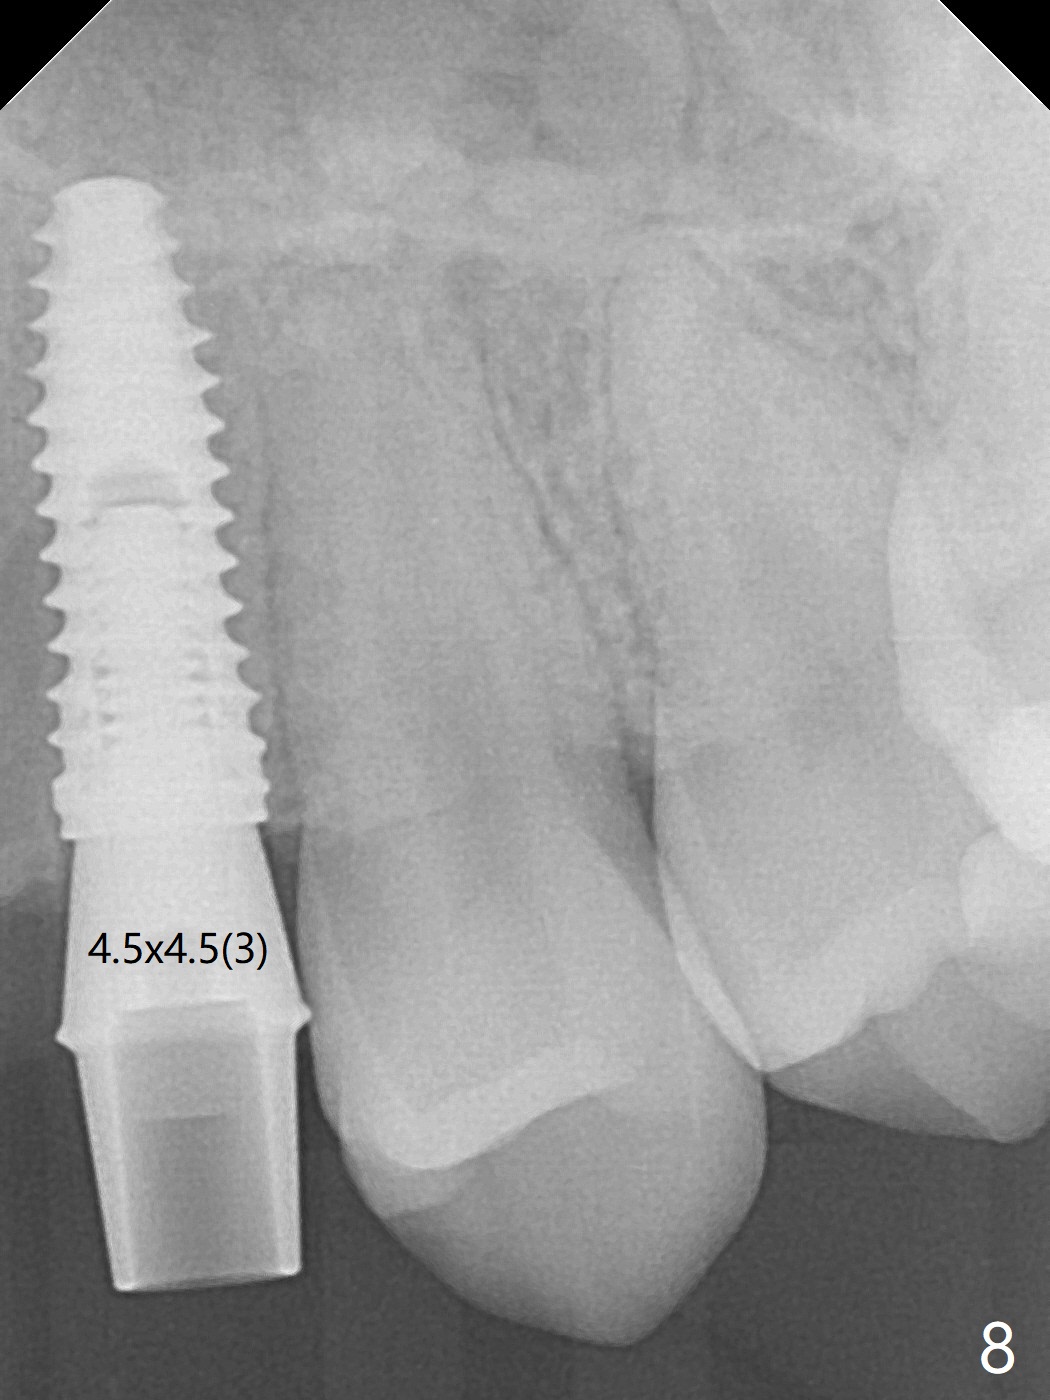

18岁男,本月底到外州上大学,急于十九岁前完成治疗,保险可以多付些。术前检查显示双侧尖牙(图一,二 6,11)根尖,侧切牙牙槽嵴萎缩(*),尖牙、侧切牙之间颊侧做垂直切口,骨膜下潜行分离,在尖牙根尖隧道植骨,然后使用导板,植入窄植体(图四至六),接近或者穿过上颌窦底板(图三,四箭头),骨粉(粘性骨块做的不成功,图五,六 *)好像覆盖暴露的螺纹。再次补充隧道骨粉后,放置修复基台(图七,八),调整后(图九),取模做临时悬臂桥,临床上有些困难分配尖牙,侧切牙比例。术后4个月左侧植体愈合正常(图十,十一),而右侧感染。